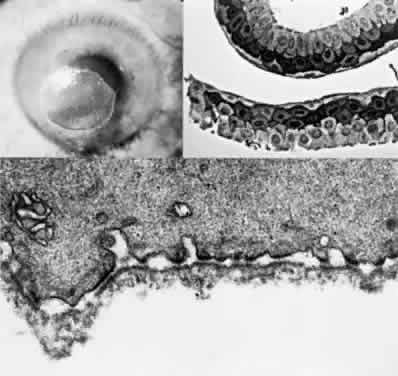

OCULAR FINDINGS. The outstanding clinical feature common to all three phenotypes is the corneal and conjunctival cystine crystal deposition (Figs. 3 and 4). Photophobia is often the only presenting visual symptom; this may be incapacitating and associated with blepharospasm.

Fig. 4. Cystinosis. Top, Transmission electron micrograph showing a stromal keratocyte containing a number of needle-shaped crystalline profiles limited by unit membranes. (× 19,000.) Bottom, Electron micrograph of conjunctival fibrocyte revealing crystalline profiles of sparse granular material within membrane-limited lysosomes. (× 30,000.) (Courtesy of Dr. Kenneth Kenyon)

Corneal deposits appear as a layer of homogeneously distributed, fusiform or needle-shaped, iridescent crystals situated in the stroma beneath the epithelium. In the infantile form, anterior crystal deposition begins early in life (between 6 and 15 months of age) and proceeds posteriorly as the patient ages; deposition advances more rapidly in the periphery. The anterior location of the crystals may be associated with recurrent erosions.33 The depth of the stromal deposition and the density of crystals is always greater peripherally than centrally. More and larger crystals occur in the superficial stroma. No visual impairment occurs at this early stage. By the age of 7 years, most patients have crystals, either within or on the endothelial surface34,35; markedly decreased corneal sensitivity is also present.36 The spherical contrast sensitivity function is significantly lower in infantile cystinosis than in age-matched controls.37